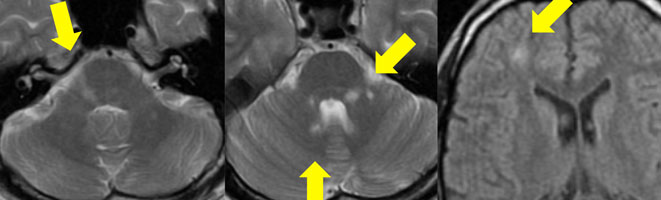

本棚にしまっていましたが使用しないので出品します。書き込みありません。非裁断です。「脳MRI 2 代謝・脱髄・変性・外傷・他」高橋 昭喜定価: ¥ 12000#高橋昭喜 #高橋_昭喜 #本 #自然/医療・薬学・健康| カテゴリー: | 本・雑誌・漫画>>>本>>>健康・医学 |